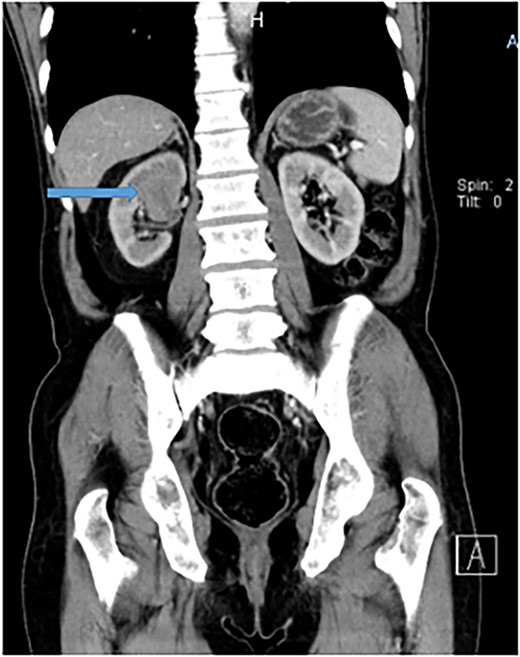

The chest and abdomino-pelvis CT scan demonstrated a well-defined tumor mass at the supero-posterior right kidney pole that measures 3.6 × 4.1 × 4.9 cm with peri-hilar lymphadenopathy (Fig. 2). Other visceral organs appeared normal. There was no evidence of metastasis. A diagnosis of renal cell carcinoma was suggested. The patient was counseled for a nephrectomy and bilateral total orchiectomy (BTO), which were successfully performed. He was kept on bicalutamide (casodex), antibiotics, and other supportive care.

Abdomino-pelvis CT scan demonstrating a well-defined tumor mass at the supero-posterior right kidney pole that measures 3.6 × 4.1 × 4.9 cm.